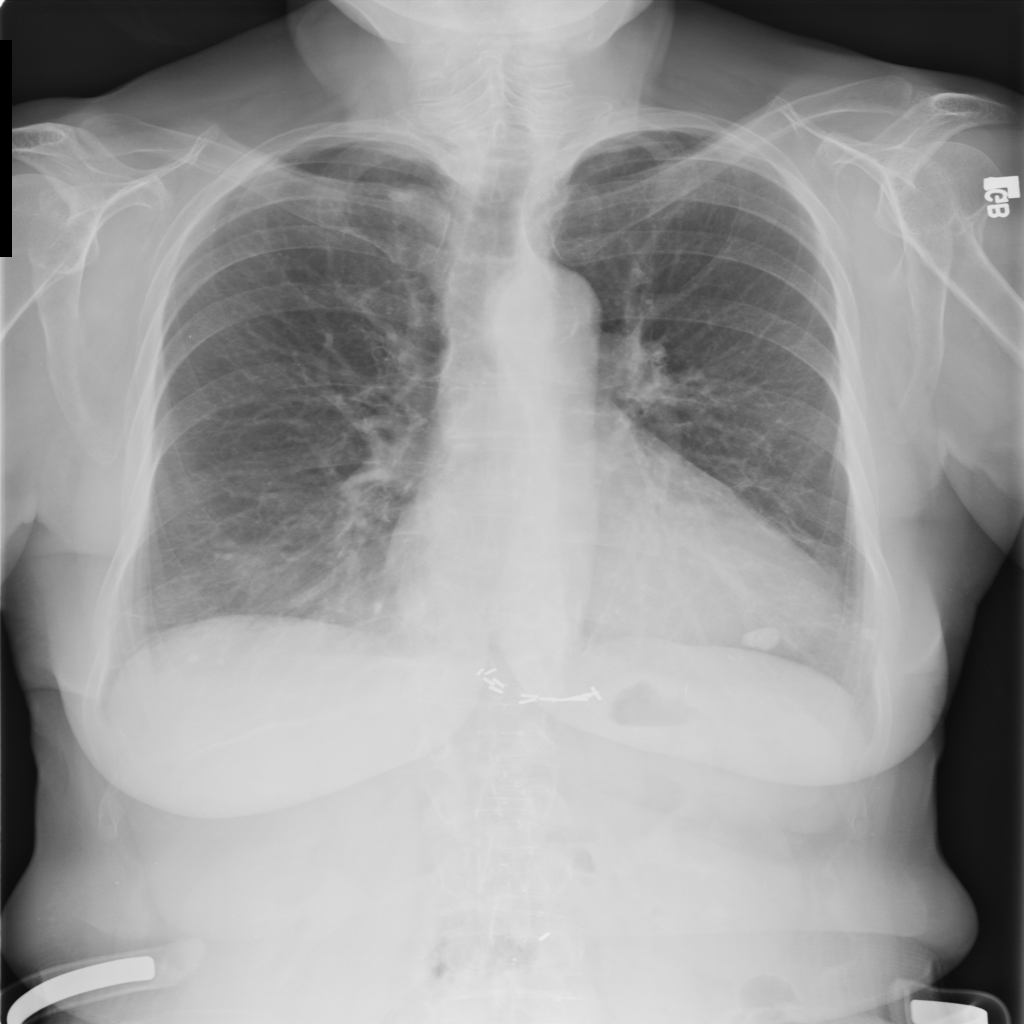

PAT-4639 · IMG-045Cardiomegaly

PAT-4639 · IMG-045

PA